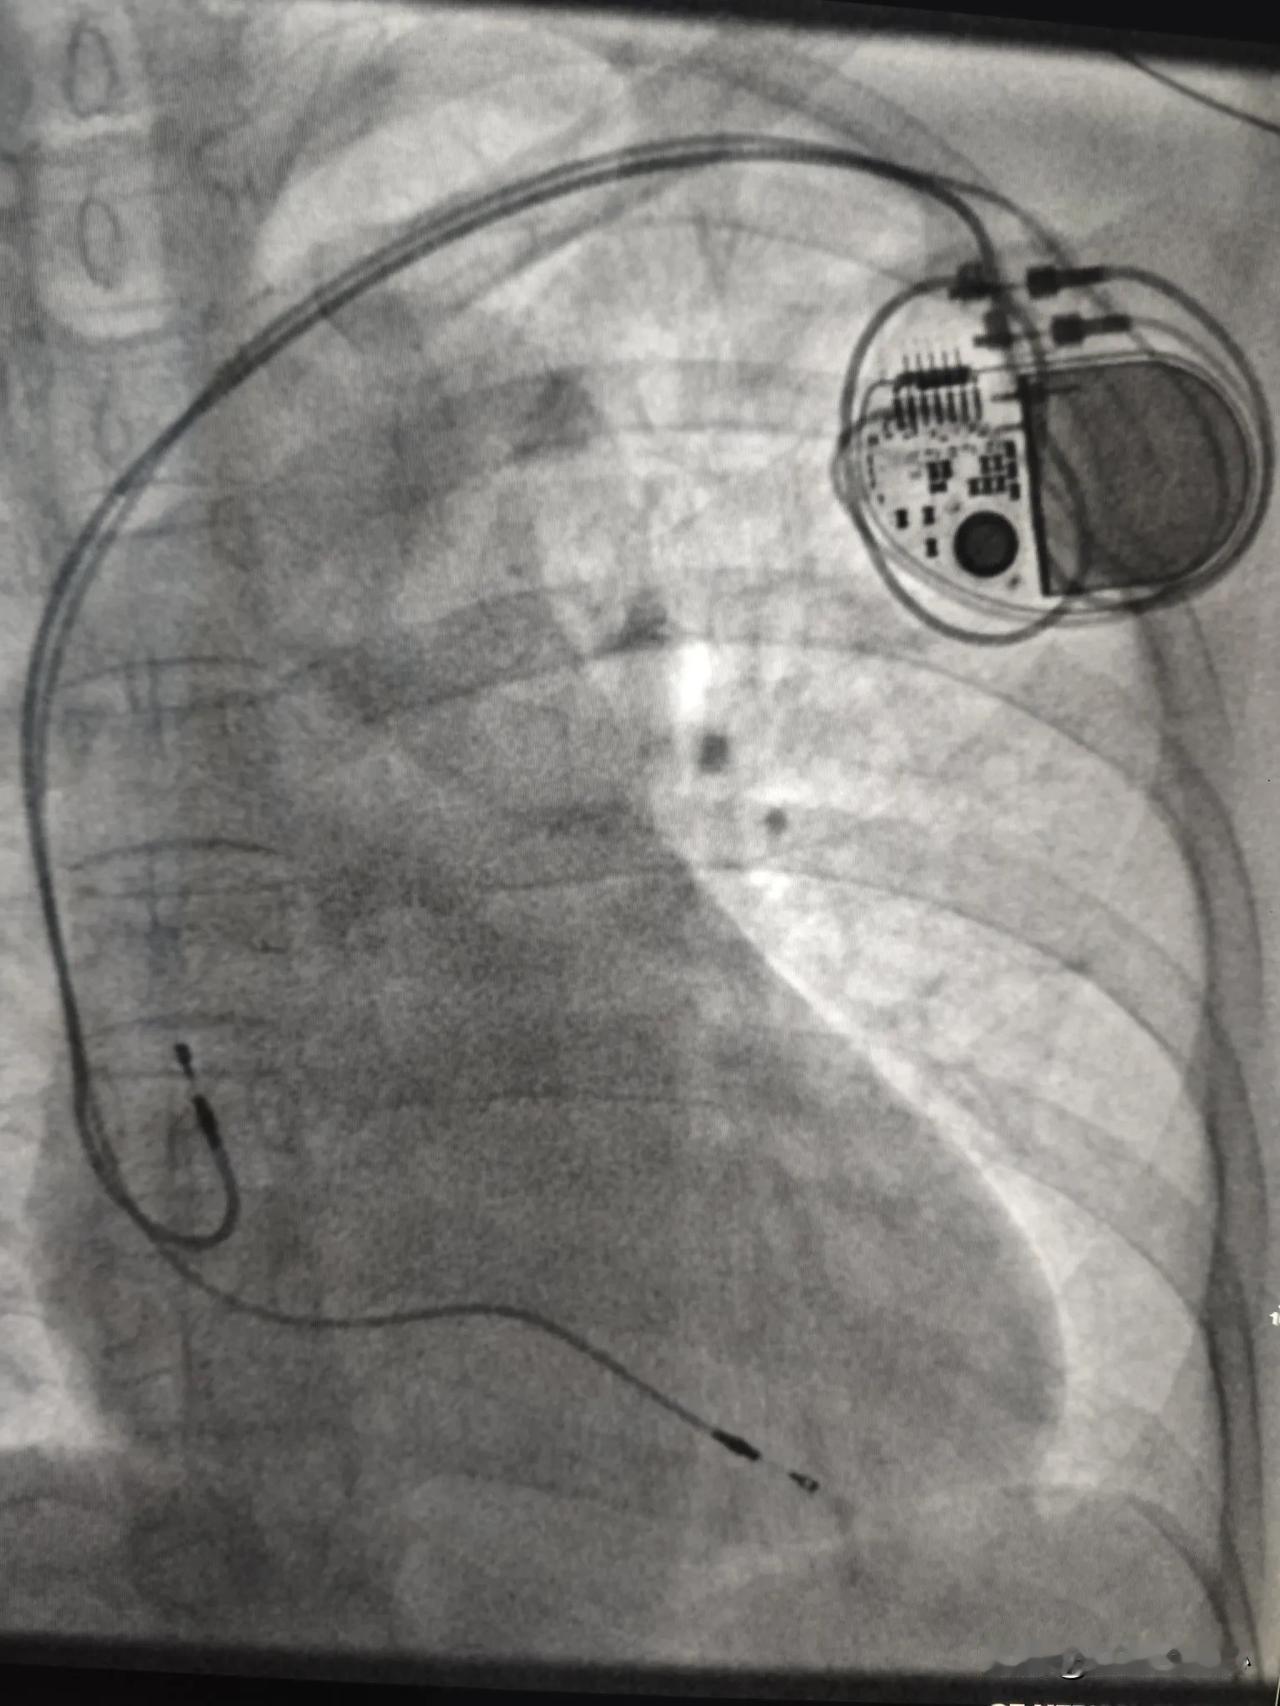

今天没有做冠心病相关手术,今天做了3台心脏起搏器手术。 第 1 台是一名65岁女性患者,体检发现心动过缓,最慢心跳每分钟29次,有高血压病史,合并有胸闷感觉,经常看科普的朋友都知道,这么慢的心率很容易引起晕厥和心脏骤停。今天在局麻下做了双腔心脏起搏器,连接心脏起搏器和导线的一刻,心跳恢复到每分钟60次。听到监护仪上规律的滴滴声,满满的安全感,再也不用担心突然晕厥了。 第 2 台是一个8年前植入心脏起搏器老年患者,因起搏器电池耗竭,更换了新的起搏器,简单说就是心脏起搏器没电了,换了一个新的起搏器。 第 3 台是一个35岁青壮年男性。这个患者病情最特殊,他很年轻只有35岁。这么年轻心衰却很严重,左心室已经扩大到7.7厘米了,正常左心室只有5厘米左右。住院后多次监测到该患者出现室性心动过速。室性心动过速是一种非常危险的心律失常,如果没有及时恢复心率,患者生命随时就会终结。在医院可以用电除颤终止这种恶性心律失常,在家里如果发作了怎么办?没有及时电除颤,患者极有可能会猝死。最好的办法就是植入ICD(植入型体内除颤仪)。这种除颤设备体积很小,只有半个手机大小,放置在左侧锁骨下方的皮肤下面,电极连接到心脏,时刻监测患者的心律情况,一旦发现室性心动过速,即可发放电脉冲终止这种危险的心律失常,成为患者存活的最后一道防线,希望他健康地活着。